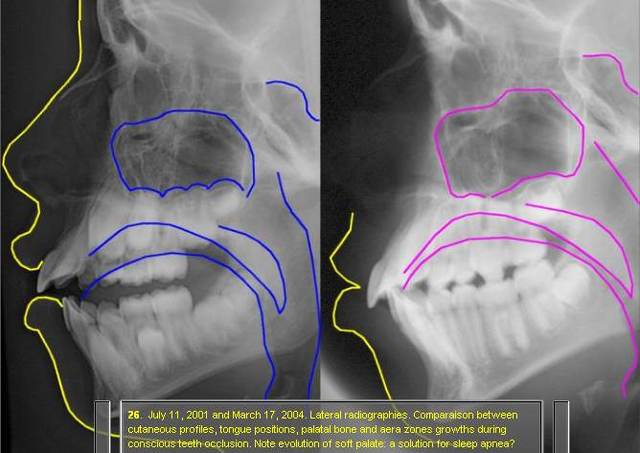

les rx ont elles ete prises dans les meme conditions? la premieres en innoclusion et la deuxieme dents serrees?

L'ANB s'est surtout réduit..parce que le patient ferme la bouche sur la deuxieme radio! -donc le point B "avance" et l'angle se réduit). La premiere radio n'est vraiment pas exploitable, l'inocclusion est complète.

-reduction de ANB par recul du point A(par rapport au Nasion)

-l'occlusion de la premiere photo est incomplete evidemment car c'est un cas d'interposition de la langue en position d'occlusion de repos(je n'invente rien,je lis"conscious occlusion"), cas de deglutition infantile avec beance anterieure

(d'accord avec toi,pas de succion de pouce)

-moi j'ai mesure ANB= 4.5,ce qui est une classe 1 acceptable?

-oui a la compensation dentoalveolaire des incisives qui se touchent enfin